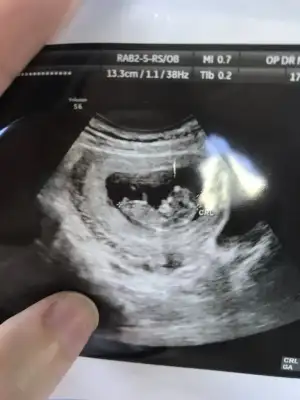

Nubu yüksek görünüyor sanki net değil karışık görünüyor emin olamadimBaşka usg yok doktor kıza benziyor demisti ama net değil demisti

Canım 11 de büyük olasılık kız 12 de nubu kalktı kız da olabilir erkek de dedi. 15 te %100 kız dedi 16 da hala kız dediSize 12.haftada doktor, erkek mi dedi?

Kız gibi sanki kaç haftalık usgler 11 12 13 haftalar olmalı

Emin olamadım başka USG varsa paylaşın sanki erkek gibi gibi ama emin değilimMerhaba 11+0 tahminde bulunur musunuz?

Birde bu var :)Emin olamadım başka USG varsa paylaşın sanki erkek gibi gibi ama emin değilim

Net değil olursa 12 13 haftalar paylasirsinBirde bu var :)

Merhaba tahmininiz doğru çıktı doktorumuz %95 kız dediDr tam -----+ nubtan geçmiş ölçümü emin değilim sanki kız 11 12 13 haftalar olursa paylasin